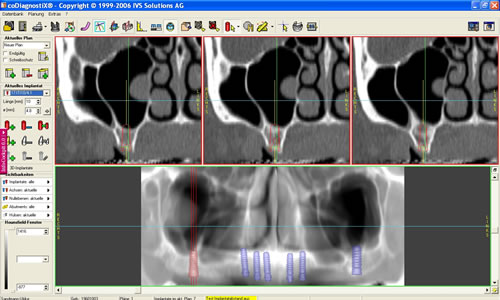

Mit der Entwicklung der Computertomographie (CT) und in jüngerer Vergangenheit der digitalen Volumentomographie (DVT) stehen Untersuchungsverfahren zur Verfügung, mit denen sehr viel einfacher und genauer das Knochenangebot vermessen werden kann. Von dem Patienten wird in einer Klinik oder Praxis, die über die entsprechenden Möglichkeiten verfügt, ein Spezialröntgenbild (DVT/CT) des Ober-, seltener des Unterkiefers, angefertigt. Dieses spezielle Röntgenbild dauert für einen Kiefer 20 Sekunden. Der große Vorteil liegt darin, dass der gesamte Kiefer durch den Computer in über 100 Schnitten abgebildet werden kann. Auf diesen Schnittbildern können Höhe und Breite des Knochens direkt abgemessen werden (Abb. 5.5).

Nach dem Überspielen der Daten auf den Praxiscomputer des Zahnarztes eröffnen sich weitere Möglichkeiten. Der Kiefer wird in verschiedenen Ebenen gleichzeitig dargestellt und damit eine räumliche Auswertung möglich. Neben der Vermessung des Kiefers kann die Knochenqualität durch Dichtemessungen beurteilt werden. Damit lässt sich z.B. eine bestimmte Knochenerkrankung, die Osteoporose, nachweisen bzw. ausschließen.

Am Praxiscomputer lassen sich Besonderheiten des jeweiligen Patienten herausarbeiten, wie z. B. die Beschaffenheit der Nasennebenhöhle. Hier können verschiedenen Knochenleisten (Abb. 5.6) oder Schleimhautveränderungen das Implantieren erschweren. Umso wichtiger ist es durch ein Computertomogramm diese Variationen vor der Implantation zu kennen. In den speziellen Programmen können bereits Implantationen simuliert werden (Abb. 5.7, 5.8).

Abb. 5.7: Implantations- simulation am PC.

Abb. 5.8: Implantatplanung.

Dabei werden das Implantat, die richtige Länge und der geeignete Durchmesser ausgewählt. Entscheidend ist auch die Richtung, in der implantiert werden muss. Auch dies lässt sich bereits am Computer auf den Schnittbildern simulieren. Eine dreidimensionale Darstellung des Knochens und die Möglichkeit das äußere Profil zu zeigen, verdeutlichen den späteren Sitz der Implantate und die Beziehung zum Gegenkiefer, zur Kauebene, zu Wangen und Lippen lassen die spätere Versorgung kosmetisch vorhersehen (Abb. 5.9, 5.10). Eine Dichtemessung um die Implantate schließt die Planung ab.

Im Oberkiefer wird diese Untersuchung und Planung in unserer eigenen Praxis seit Jahren routinemäßig durchgeführt. Die erheblich verbesserten Ergebnisse rechtfertigen den Mehraufwand, die geringfügig höhere Strahlenbelastung der heutzutage modernen Geräte sowie die Kosten, die dadurch entstehen.

Für den Oberkiefer ist eine CT-Untersuchung notwendig, die ebenfalls mit einer Schablone durchgeführt wird. Auswertung, Planung und Implantations-Simulationen ergeben, dass sechs Implantate im vorderen Kieferabschnitt verankert werden können. Auch die Qualität des Knochens lässt eine Einpflanzung ohne weitere Maßnahmen zu. Diese Behandlung soll nach der Versorgung des Unterkiefers erfolgen.